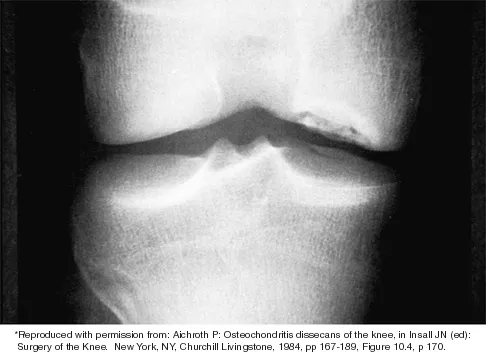

Question 46

Which of the following primary prognostic factors best predicts the outcome of the knee lesion shown in Figure 22?

Explanation